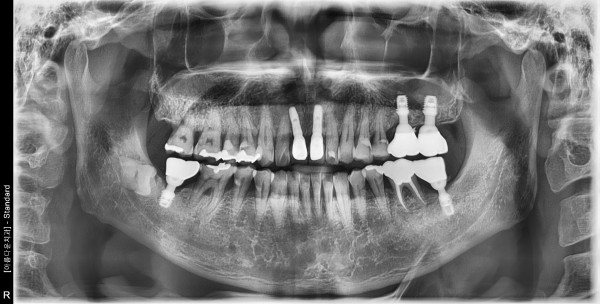

50대 남성 임플란트 식립

8a08f77c64fcbf7fd4a8101c03ab8c69_1760922